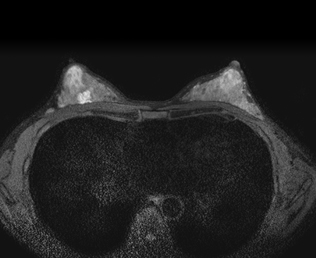

현재 유방암 치료가 발달하여 유방의 일부만을 제거하는 보존술식이 점점 많이 행해지고 있습니다. 유방암으로 진단되었다고 해서 바로 수술을 받으시는 것이 아니라 암의 위치나 크기가 어떠한지 다른 부위의 이상 소견은 없는지 미리 아는 것이 이러한 보존술식에 중요하여 진단 받으시고 치료받으시기 전에 다양한 유방영상검사를 받으시게 됩니다. 본원에서 유방영상검사는 방사선과의 유방을 전공으로 하는 전문의에게 받게 되시며 X-선을 이용한 유방촬영뿐 아니라 유방초음파, 유방자기공명영상, 초음파유도하 유방중심부침생검도 영상의학과에서 받게 됩니다. 또한 치료 후 추적검사를 규칙적으로 또는 필요에 따라 시행 받으시게 됩니다.